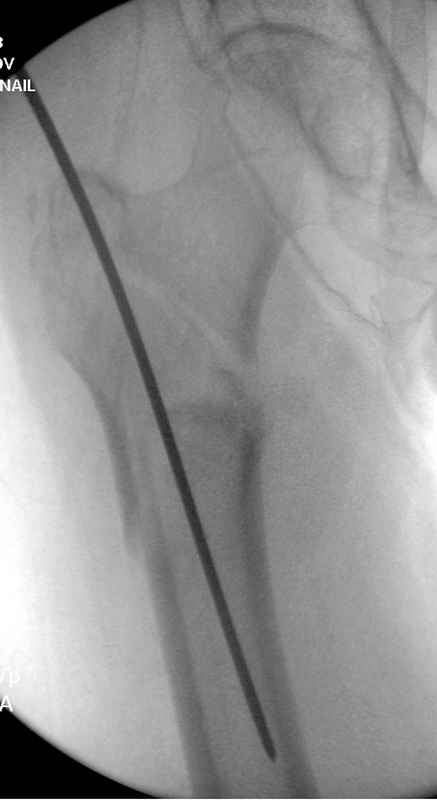

Здесь пара случаев фиксации похожих переломов:

первый высокоэнергетическая травма 36 лет